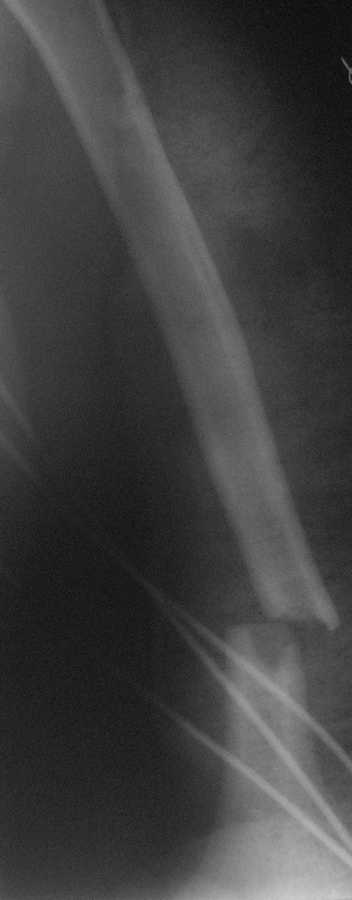

Пациентка 50 лет. Находится на лечении с Сочетанной травмой. ОЧМТ.Ушиб головного мозга и перелом основания черепа. Множественные переломы ребер. Закрытый перелом н\3 плечевой кости. В настоящее время состояние пациентки стабильное. Подскажите какую тактику лечения лучше применить в данном случае.